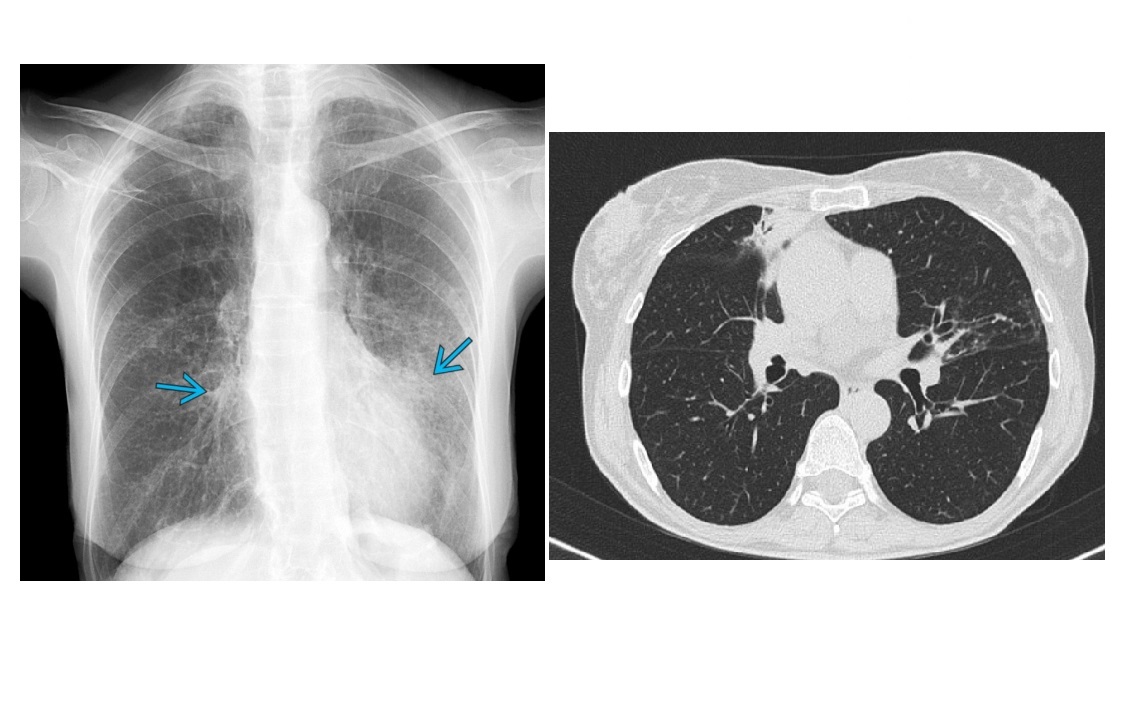

MAC

Tree in bud - terminal bronchiole filled with radiopaque material

cylindric bronchiectasis

clasically right middle lobe or lingula (aka lady windermere syndrome)